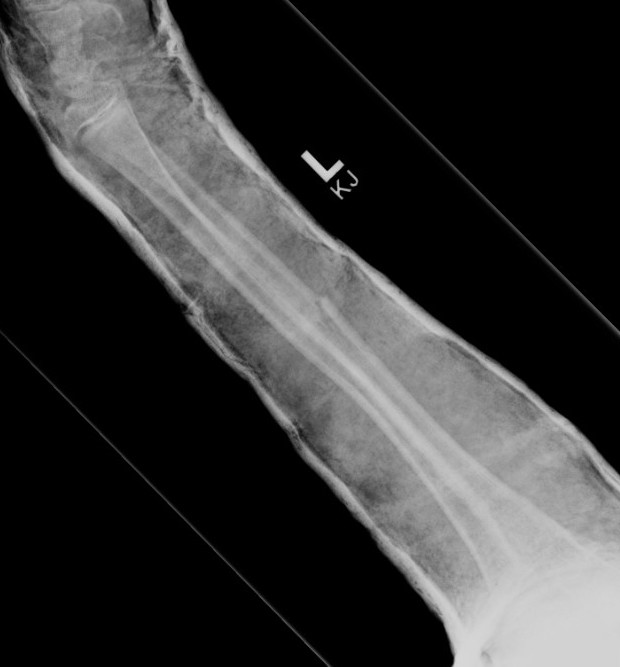

3. Intramedullary elastic nail

- smaller scars with insertion

- easier to remove than plates

Disadvantage

- generally immobilized

- must be removed

- non anatomical reduction compared with plates with theoretical risk of loss supination / pronation

- risk of extensor tendon rupture due to prominence of nails at insertion sites

TENS technique

Technique

Radius (typically first as more difficult to reduce)

Entry point with awl 2 cm proximal to distal physis

1. Radial styloid / distal lateral entry

- ensure radial nerve / cephalic vein, 1st extensor compartment protected

2. Listers tubercle / dorsal entry

Elastic Nail size

60 - 70% of the intramedullary canal

Typically 1.5 - 2.5 mm

Fracture reduction

Avoid passing nails incorrectly multiple times as may cause compartment syndrome

Bend tip of elastic nail

May need small open reduction

Cut nail

Withdraw 1 cm, cut with endcutter, then advance

Ulna (usually reduced after radius fixation)

Entry point 2 cm distal to apophyseal plate

1. Proximal lateral

- avoids ulna nerve

3. Distal medial

Postoperative

Cast in supination to tighten interosseous membrane

Cast 6 weeks

Removal of TENS at 4 - 6 months once osseous union established